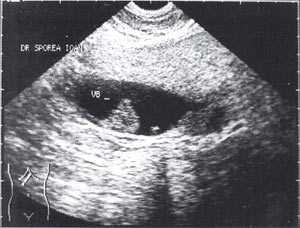

Кроме типичного вида, "желчный сладж" может иметь особый вид, похожий на круглое полипоидное объемное образование с острыми краями или неравномерным контуром ("опухолеподобный желчный сладж" или "сладжевые шарики" [12, 13]). При изменении положения больного видны перекатывающиеся или разрушающиеся шарики сладжа, затем снова формирующие исходное объемное образование (рис. 2-8).

Рис. 2. Желчный пузырь, наполовину заполненный сладжем.